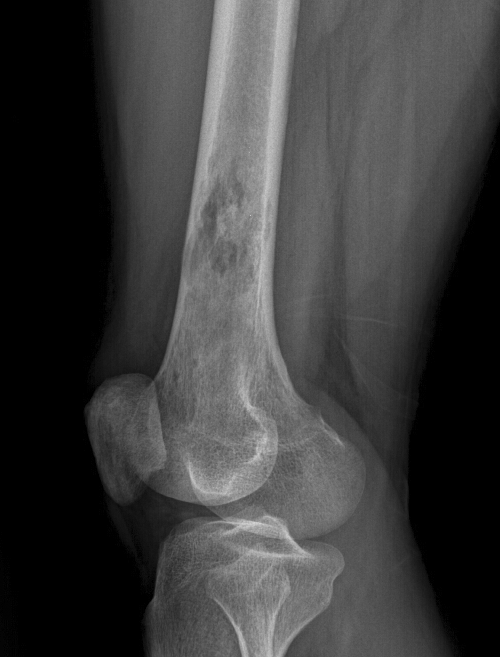

肿瘤对软骨的破坏

肿瘤对骨骺板和关节软骨的破坏是对骨破坏的继续。缺乏血管的骨骺板对恶性肿瘤有抵抗作用,骨骺板可暂时阻止肿瘤的蔓延,但当肿瘤进一步发展时, 骨骺板亦可被破坏,X 线平片或 CT 可表现为先期钙化带密度减低、中断或消失。MRI 可显示肿瘤从干骺端跨越骨骺板侵犯骨骺(图 15、图 16)。肿瘤突破关节软骨向关节腔发展时, 可表现为关节面破坏、塌陷(图 17), 关节腔内出现软组织肿块。少数良性骨肿瘤如软骨母细胞瘤, 亦可超越骺板向两侧发展或突入关节腔内, 此为肿瘤膨胀生长所致, 而非浸润性破坏。

图 15.骨骺板破坏:骨肉瘤

图 16.骨骺板破坏:骨肉瘤